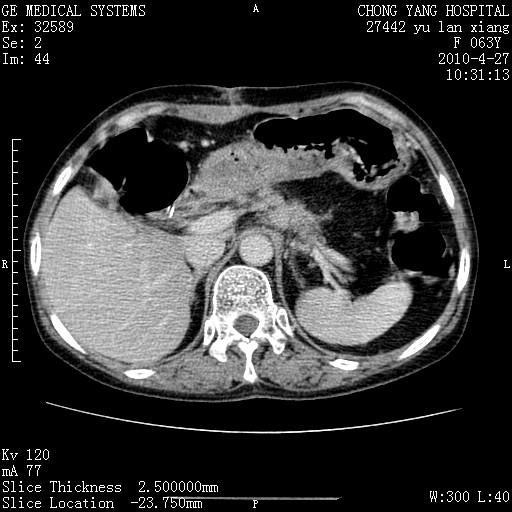

标题: CT26066:F63Y 上腹正中压痛半月,CA199:7400u/ml,MR示胰腺炎伴 [打印本页]

胰腺癌侵犯腹腔动脉干-分支、胃壁、左侧膈肌伴胰周及腹膜后淋巴结转移、胆囊切除术后。

胰腺癌侵犯腹腔动脉干-分支、胃壁、左侧膈肌伴胰周及腹膜后淋巴结转移、胆囊未显影。